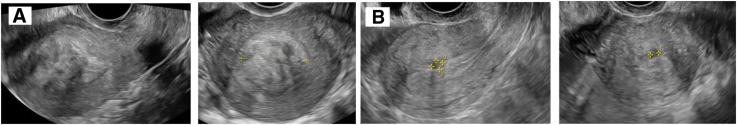

经阴道射频消融术:一种治疗有生育意愿的有症状子宫肌瘤女性的治疗选择。

Transvaginal radiofrequency ablation: a therapeutic option for managing symptomatic uterine fibroids in women with reproductive desires.

To evaluate whether transvaginal radiofrequency (RF) ablation of fibroids is a technique that can be offered to women with reproductive desires.

Transvaginal RF ablation for symptomatic fibroids with a maximum total volume of 145 cm.

The reduction in the size of the fibroids, improvement of symptoms, and reproductive outcomes during the 24 months after the ablation. For patients who achieved pregnancy, we assessed the type of conception, course of gestation, type of delivery, neonatal outcomes, and occurrence of both maternal and fetal complications.

A statistically significant reduction in symptoms related to the fibroids 6 months after the ablation was demonstrated through the implementation of the Symptom Severity Scale. No patient required hospitalization after the procedure, and on average from the third day after intervention, they resumed their work activities without the need for analgesics. Among those patients who attempted pregnancy during the 24-month follow-up period, 73.68 % (14/19) achieved motherhood. There were no cases of uterine rupture, premature birth, or intrauterine fetal death.

Radiofrequency ablation for fibroids seems to be a promising, safe, and low-complexity alternative that does not appear to interfere with the development of a normal term gestation.